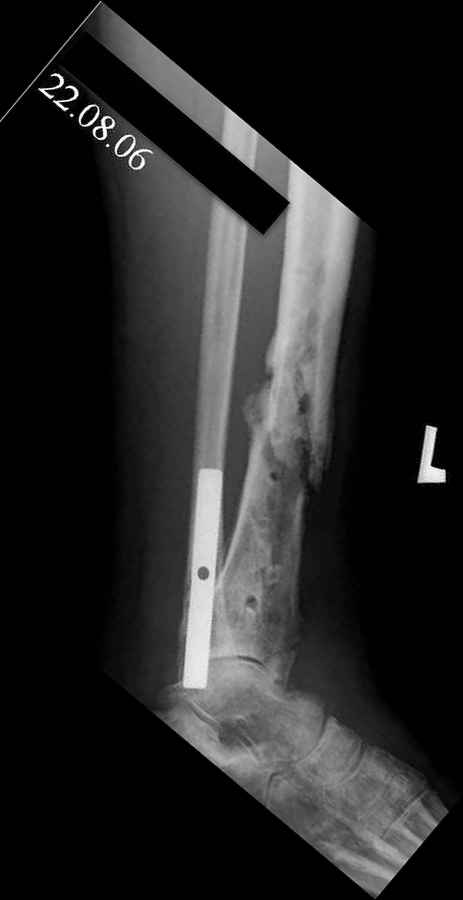

Владимир, свободная костная пластика на фоне свища вряд ли оправдана. Почему не рассматриваете вариант транспорта кости по Илизарову? Что собираетесь делать с латентной инфекцией? Одни антибиотики не помогут, необходима полноценная хирургическая обработка, Мы бы подумали о цементном спейсере с антибиотиками, бусах. После купирования инфекции переходить к замещению

дефекта: за счет удлинения концов б\б кости или тибиализации м\б. На начальном этапе фиксация только в аппарате, в последствие для удержания достигнутого можно перейти на фиксацию интрамедуллярным штифтом (см. вложенные файлы)

Как дополнение высылаю снимки и фото конечности, чтобы Вы могли оценить состояние м/т, и течение заболевания.